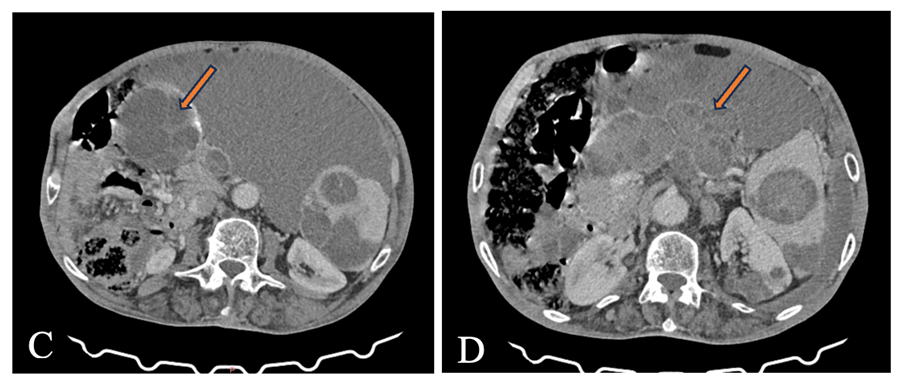

- CT imaging revealed multiple well-defined cystic formations with thin, regular walls and heterogeneous internal content, consistent with hydatid cysts. Several cysts showed areas of varying density, corresponding to daughter vesicles and detached membranes, producing the characteristic “water-lily” and “rosette” appearances. These lesions were distributed in the mediastinum, peritoneal cavity, spleen, and both kidneys, causing mass effect on adjacent structures without signs of invasion. Some cysts demonstrated calcified walls, suggesting chronic evolution, while others retained a typical fluid density, indicating different stages of disease activity.

Figures: Abdominal CT scan with contrast injection, showing multiple intraperitoneal cystic formations in the right flank (Figure C) and the antro-pyloric region (Figure D).